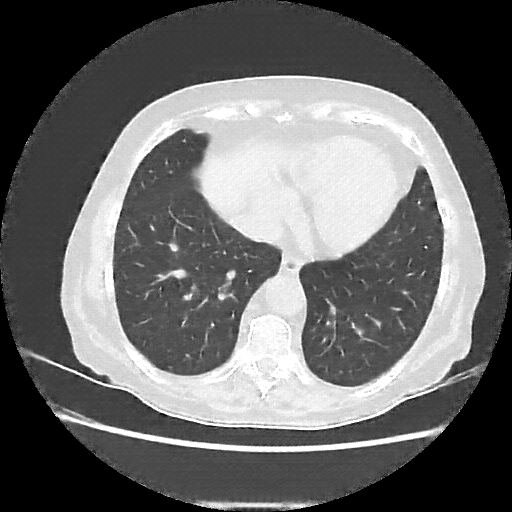

Original NATIVE CT scan (input)

Full window (WL 1023.5, WW 4095 β†’ Low βˆ’1024, High +3071)

Lung window (WL -600, WW 1500 β†’ Low βˆ’1350, High +150)